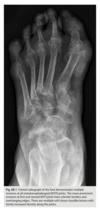

Foot pain

A lateral radiograph of the left foot demonstrates a prominent talar beak

­ (arrow) and bony sclerosis overlying the middle

facet (arrowheads). Coronal CT through the middle

facet shows talocalcaneal fusion, with bony bridging between the talus and the sustentaculum tali of the

calcaneus

Diagnosis: Tarsal coalition

abnormal fusion

of one or more of the tarsal bones, may be fibrous,

cartilaginous, or osseous and may be posttraumatic, or congenital.

Most

common tarsal coalitions are calcaneonavicular and

talocalcaneal.

Radiographically, calcaneonavicular coalition may

be suspected because of elongation of the anterior

facet of the calcaneus on radiographs (i.e., anteater

sign. CT can also be used to confirm coalition and shows

­ sclerosis at the articulation

Congenital coalition usually evolves from fibrous to osseous

coalition and may not be apparent on the initial

evaluation

Talocalcaneal coalition can result in dorsal beaking

of the talar head (Fig. 2.3.6, arrowhead), the so-called

C-sign (arrows)